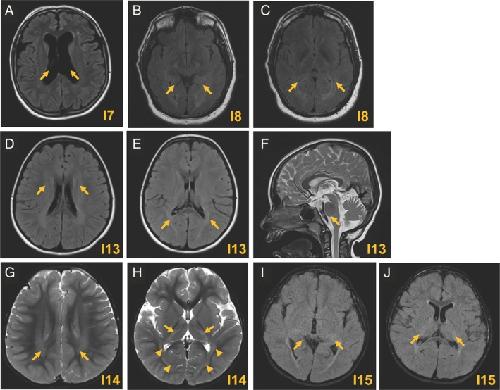

HCN2-Associated Neurodevelopmental Disorders: Data from Patients and Xenopus Cell Models.,

Houdayer C,Phillips AM,Chabbert M,Bourreau J,Maroofian R,Houlden H,Richards K,Saadi NW,Dad'ová E,Van Bogaert P,Rupin M,Keren B,Charles P,Smol T,Riquet A,Pais L,O'Donnell-Luria A,VanNoy GE,Bayat A,Møller RS,Olofsson K,Jamra RA,Syrbe S,Dasouki M,Seaver LH,Sullivan JA,Shashi V,Alkuraya FS,Poss AF,Spence JE,Schnur RE,Forster IC,Mckenzie CE,Simons C,Wang M,Snell P,Kothur K,Buckley M,Roscioli T,Elserafy N,Dauriat B,Procaccio V,Henrion D,Lenaers G,Colin E,Verbeek NE,Van Gassen KL,Legendre C,Bonneau D,Reid CA,Howell KB,Ziegler A,Legros C,

Ann Neurol. September 5, 2025; 98(3):1531-8249.